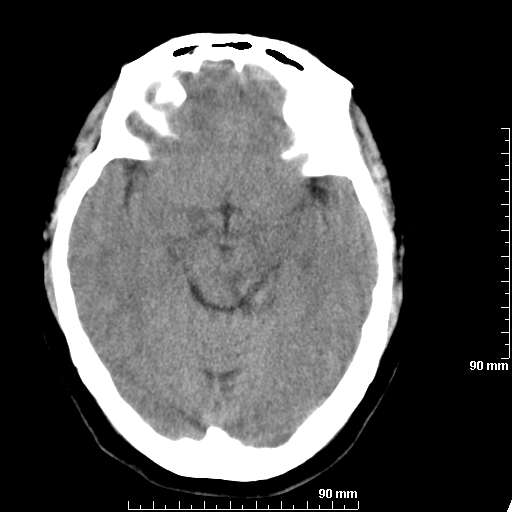

[维修案例解析] 大家猜猜看,这个伪影是怎样产生的.

二马日王 显示全部楼层 发表于 2011-6-9 18:12:55 |阅读模式

我院西门子单排CT由于一零件受损而产生的伪影.

哈哈,都不是。是虑线器fiter裂损。大家没想到吧。

哦,跟脑出血有点像哦

形状不规则,边缘模糊。比较特殊的一种伪影哈!

这种伪影很常见!伪影应该是在视野的中心的。

西门子的虑线器fiter裂损这才是很难见的问题,GE的最常见

虑线器老化,中间崩裂一块掉了